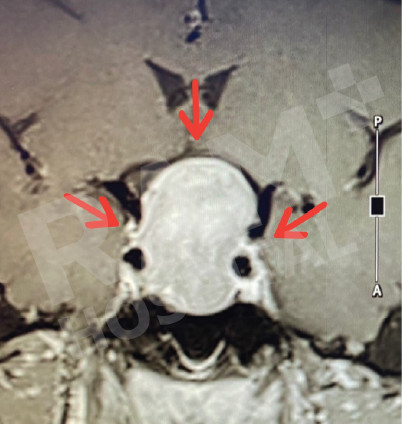

磁共振成像(MRI)可清晰、细致地显示垂体的异常病变,精准定位垂体腺瘤的位置;结合静脉造影增强检查,还能明确腺瘤的具体位置与病变性质,同时清晰呈现脑部周边组织及鼻窦的情况。这一项检查结果可为制定诊疗方案、随访评估垂体腺瘤的治疗效果,乃至规划手术方案提供明确、可靠的依据。